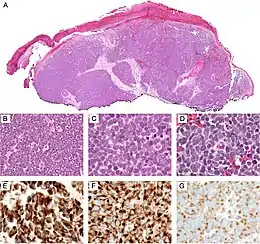

Characteristics

Basal-cell carcinoma cells appear similar to epidermal basal cells, and are usually well differentiated.[25]

In uncertain cases, immunohistochemistry using BerEP4 can be used, having a high sensitivity and specificity in detecting only BCC cells.[26]

Basal-cell carcinoma can broadly be divided into three groups, based on the growth patterns.

- Superficial basal-cell carcinoma, formerly referred to in-situ basal-cell carcinoma, is characterized by a superficial proliferation of neoplastic basal-cells. This tumor is generally responsive to topic chemotherapy, such as imiquimod, or fluorouracil, although surgical treatment is better able to ensure complete removal and confirm that there is not an underlying more aggressive subtype that was not sampled in the initial biopsy.

- Infiltrative basal-cell carcinoma, which also encompasses morpheaform and micronodular basal-cell cancer, is more difficult to treat with conservative methods, given its tendency to penetrate into deeper layers of the skin.

- Nodular basal-cell carcinoma includes most of the remaining categories of basal-cell cancer. It is not unusual to encounter heterogeneous morphologic features within the same tumor.

Nodular basal-cell carcinoma (also known as "classic basal-cell carcinoma") accounts for 50% of all BCC.[27] It most commonly occurs on the sun-exposed areas of the head and neck.[28]: 748 [29]: 646 Histopathology shows aggregates of basaloid cells with well-defined borders, showing a peripheral palisading of cells and one or more typical clefts.[27] Such clefts are caused by shrinkage of mucin during tissue fixation and staining.[30] Central necrosis with eosinophilic, granular features may be also present, as well as mucin. The heavy aggregates of mucin determine a cystic structure. Calcification may be also present, especially in long-standing lesions.[27] Mitotic activity is usually not so evident, but a high mitotic rate may be present in more aggressive lesions.[27] Adenoidal BCC can be classified as a variant of NBCC, characterized by basaloid cells with a reticulated configuration extending into the dermis.[27]

There are mainly three patterns of aggressiveness, based mainly the cohesion of cancer cells:[33]

| Low-level aggressive pattern | Moderately aggressive pattern | Highly aggressive pattern |

|---|---|---|

|

|

|